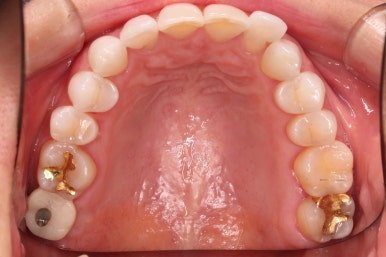

초진 시 입안의 모습입니다.

환자분이 원하셨던 부분은 윗니 작은 앞니가 하나 튀어나와서 개선하고 싶어하셨습니다.

부가적으로 아랫니 앞니가 마모가 심하여 높낮이가 달라보이는 점이었는데요.